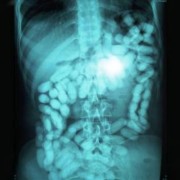

Батерии